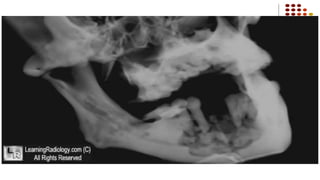

Osteomyelitis-R/F

Diffuse lytic changes in the bone begin to appear,Individual trabeculae

become fuzzy and indistinct and radiolucent areas begin to appear

Suppurative Osteomyelitis:

Radiographic Features

 Normal in early stages.

 In 10-14 days, sufficient bone

resorption occurs to produce

irregular, moth-eaten areas of

radiolucency.

 Sequestra may be seen.